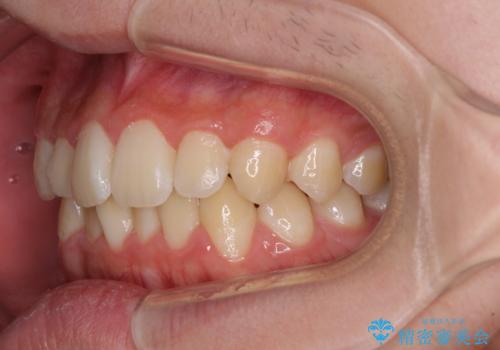

しっかり使って短期間で治療 インビザラインによる叢生解消

- 10代男性(高校生)

- インビザライン

- 9ヶ月